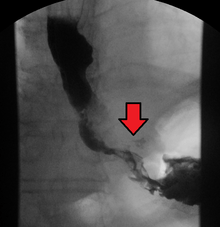

Although an occlusive tumor may be suspected on a barium swallow or barium meal, the diagnosis is best made with an examination using an endoscope. This involves the passing of a flexible tube with a light and camera down the esophagus and examining the wall, and is called an esophagogastroduodenoscopy. Biopsies taken of suspicious lesions are then examined histologically for signs of malignancy.